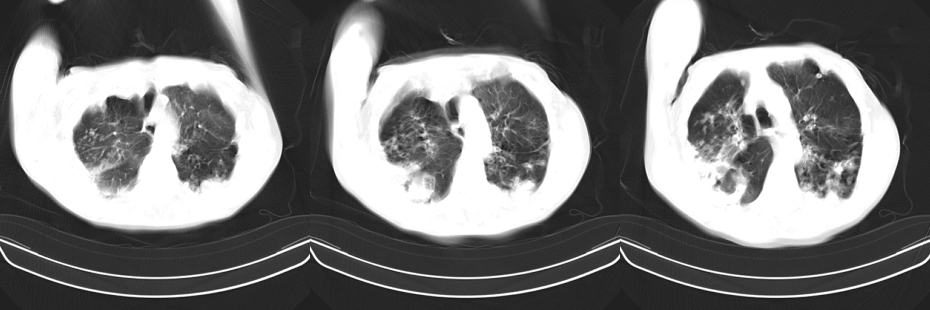

以下是引用mzh123在2007-8-26 19:58:00的发言:[br]两肺弥漫性斑片改变,其中可见大小不等之不规则空洞,结合既往病史还是考虑结核复发及感染。

以下是引用云翔在2007-8-26 20:54:00的发言:[br]这是44岁的肺吗?是否有先天病的基础?干酪性肺炎?